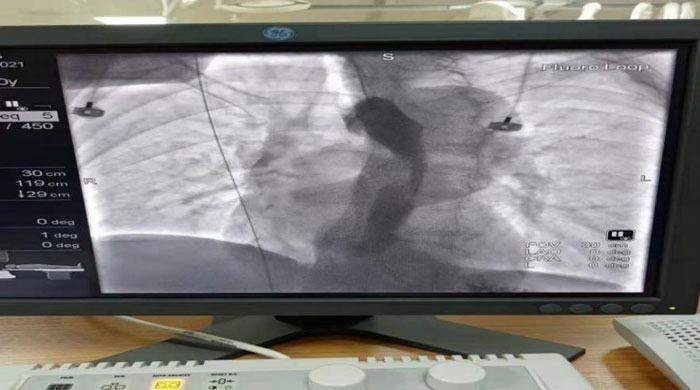

患者于2021年12月15日行“食管球囊擴(kuò)張+食管支架植入術(shù)”。術(shù)中在數(shù)字減影X光機(jī)透視下準(zhǔn)確定位示狹窄位于食管胸中段,長(zhǎng)約6CM,管腔極度狹窄,僅少量造影劑呈線型通過(guò),鉛標(biāo)標(biāo)記狹窄遠(yuǎn)近兩端;導(dǎo)絲引導(dǎo)下經(jīng)口、食道引入5f造影導(dǎo)管至胃內(nèi),造影確認(rèn)導(dǎo)管位于胃內(nèi),退出導(dǎo)管保留導(dǎo)絲,沿導(dǎo)絲引入球囊擴(kuò)張導(dǎo)管擴(kuò)張食管狹窄段。退出球囊保留導(dǎo)絲, 沿導(dǎo)絲將18mm*100mm型號(hào)食道支架放置于食管狹窄處,確認(rèn)位置合適后釋放推送器使支架擴(kuò)張,支架擴(kuò)張后退出推送器及導(dǎo)絲;再次口服造影劑可見(jiàn)食管全段通暢,支架擴(kuò)張良好,手術(shù)順利完成。

支架植入前造影,食管重度狹窄,僅少許造影劑線性通過(guò)